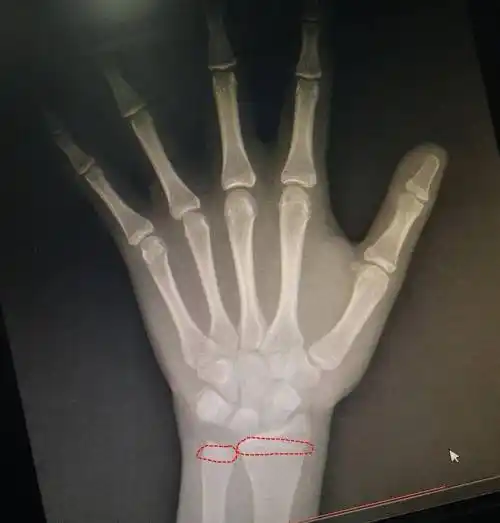

骨骺马上要闭合了结果骨龄片子拍出来一看看看还能长多高最近妈妈带着